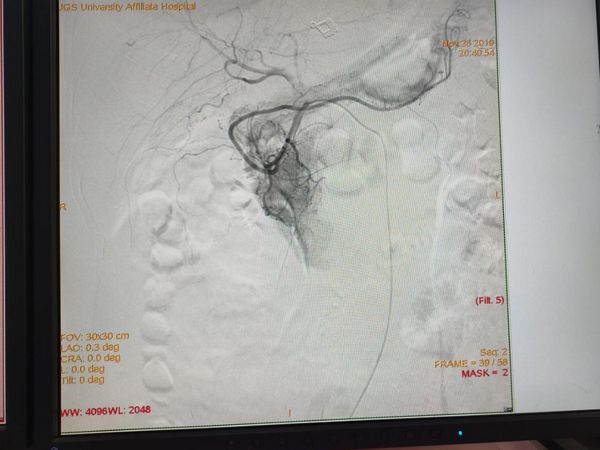

术中造影见胃十二指肠动脉末梢造影剂浓聚。明确责任血管。